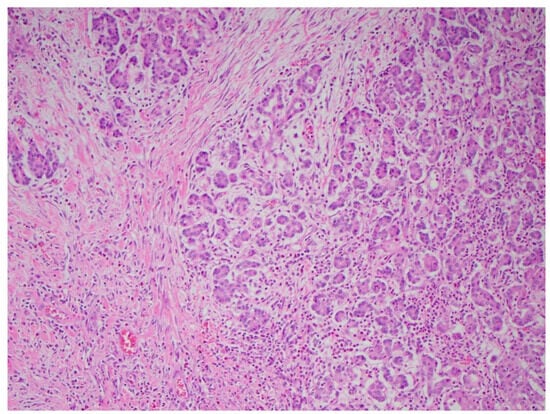

Multiple cytokines mediate a powerful pro-inflammatory immune response, such as tumor necrosis factor-alpha (TNF-a) and interleukins 1a, 1b, 6, and 18, exacerbating the initial pancreatic injury [37]. Pathologically, this appears as inflammation and can also be associated with a hemorrhage at the microscopic level (Figure 2 and Figure 3). The cytokine-mediated inflammatory cascade then extends the inflammatory cascade via lymphatic and systemic circulation into the liver, lungs, heart, kidneys, and gastrointestinal (GI) tract, leading to multi-organ injury [38]. This can cause systemic inflammatory response syndrome (SIRS), an early clinical feature that persists in cases of severe acute pancreatitis. Inflammation and damage to the GI tract can lead to bacterial translocation [39], and the species of bacteria involved are a predictive factor of disease severity, with Enterococcidae most frequently being associated with severe disease [40]. Obesity is also a predictive factor for moderate severity, and it leads to further deleterious effects through adipocyte lipolysis in the pancreas and adipose tissue [41,42] (Figure 2 and Figure 3).

Figure 2. Acute pancreatitis with hemorrhaging (H&E stain, 10×).